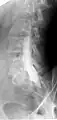

- Conventional myelography in oblique projection. You can see the individual nerve root sheaths.